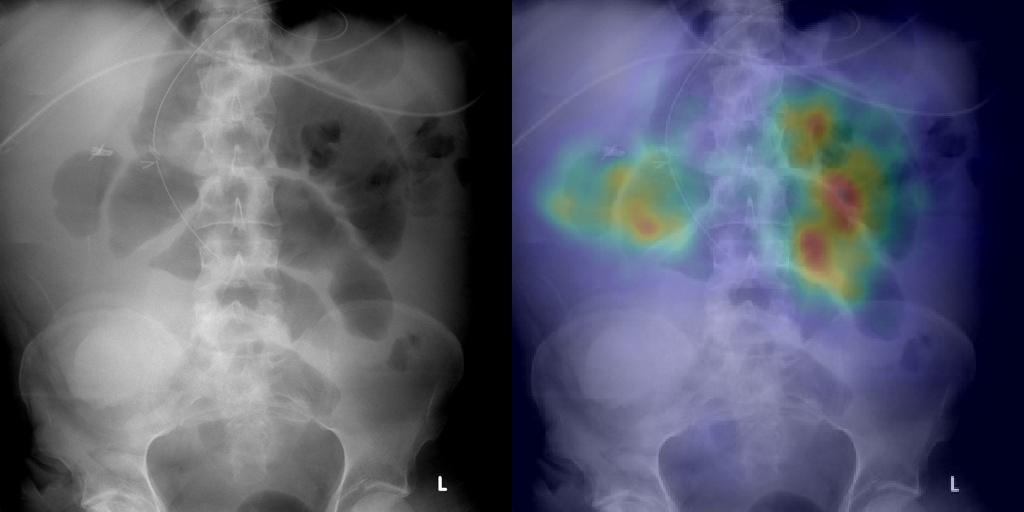

Detection of High-Grade Small Bowel Obstruction on Conventional Radiography with Convolutional Neural Networks

Studies of deep learning applied to abdominal radiographs. We show that transfer learning can be used to create a classifier for detection of high-grade small bowel obstruction patterns on supine abdominal radiographs.

Phillip Cheng, Tapas Tejura, Khoa Tran, Gilbert Whang

Abdominal Radiology 2018 (pilot study)

Am J Roentgenology 2019 (increased training)